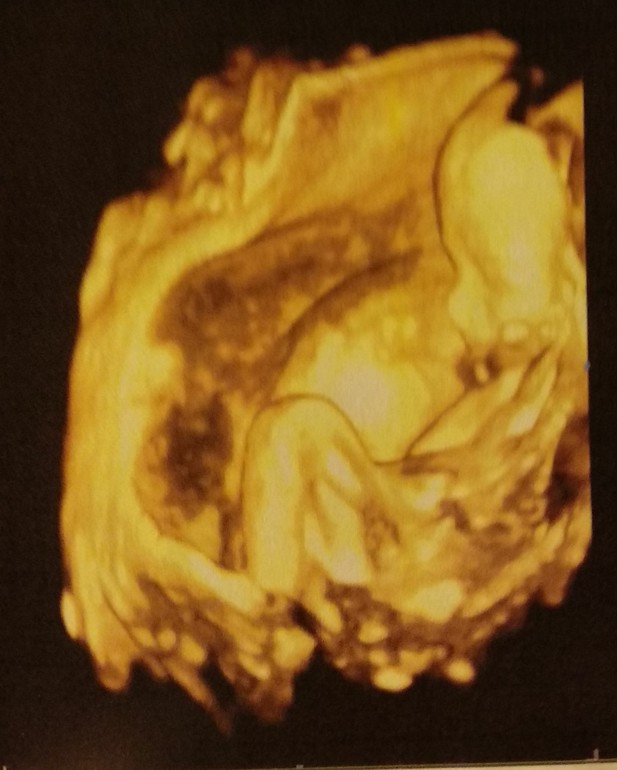

2 скрининг (20 и 4 дня)

Вертелся крутился во все стороны, фоток вменяемых меньше, чем в первый раз, но лицо уже человеческое )))

Всё у него хорошо, вес 365гр, рост 23см, сердце 148 уд\м, нос 6,1